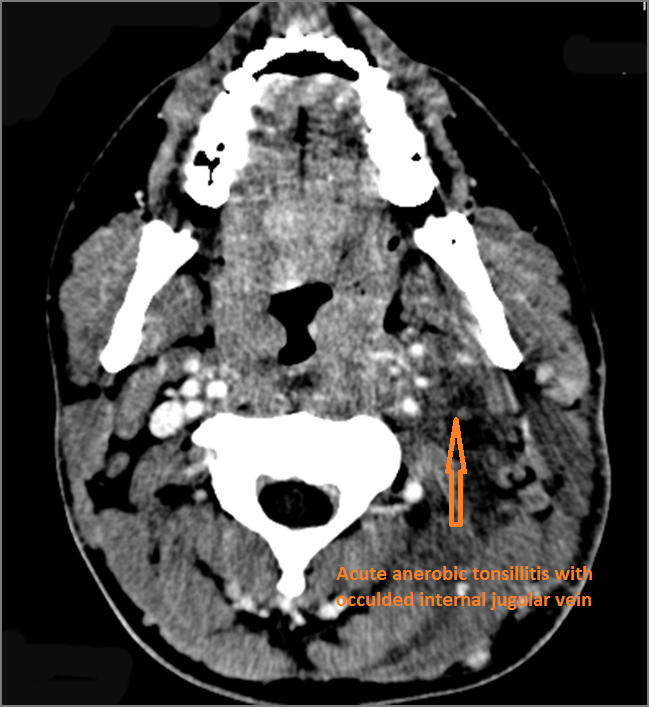

Vascular Findings

There is excessive enhancement or thickening of the mucosa or hypertrophy of the palatine or lingual tonsillar tissue or the lymphoid tissue along the glossotonsillar sulci and posterior pharyngeal wall.

There is abscess at the periphery of the lymphoid tissue of the palatine tonsil within the potential peritonsillar space.